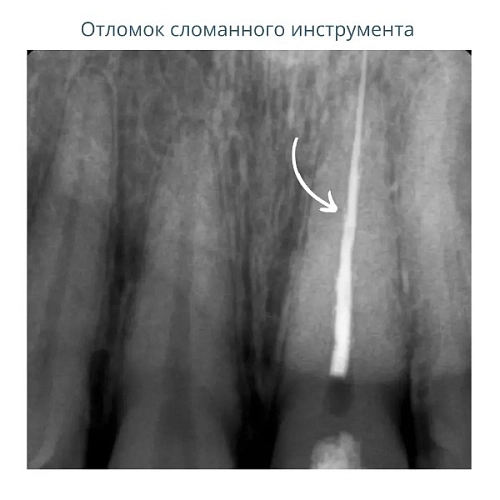

На фото представлен клинический случай.

Пациент обратился в нашу клинику с жалобой на боль при надкусывании .

При проведении первичной диагностики доктор выявил наличие сломанного инструмента в корневом канале, который привёл к воспалению.

На следующем снимке - отломок сломанного инструмента извлечён. Все каналы пройдены, механически обработаны под микроскопом и запломбированы.